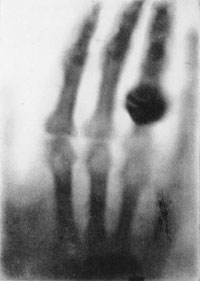

En realidad, había tomado la primera radiografía de la historia, con la pequeña particularidad de que lo hizo cinco años antes de que se descubrieran los Rayos X. Los dos discos negros que Goodspeed no pudo explicar eran la sombra de un par de objetos circulares de su laboratorio, y había sido producidos por los rayos X emitidos por el tubo de vacío. Si solamente Goodspeed hubiera investigado un poco más el fenómeno (lo hubiera repetido, hubiera buscado su causa), se habría alzado con la gloria que más tarde consiguió y aún rodea a Wilhem Roentgen, que en 1895, cuando, también experimentando con tubos de vacío, y en forma no menos casual, vio que una lámina cubierta con platinocianuro de bario, brillaba debido a la incidencia de “algo” que salía del tubo de vacío (y que él, poco más tarde, llamó Rayos X).

No faltan en relación a los rayos X. En 1894, el mismísimo J.J. Thomson, que más tarde descubriría el electrón, y que sería el primero en dar un modelo atómico nuevo desde Demócrito, vio también un resplandor a unos metros del tubo de rayos catódicos, pero no le prestó atención. Y Frederick Smith, cuando comprobó que las placas fotográficas que estaban cerca del tubo de rayos catódicos se velaban, se limitó a decirle al asistente del laboratorio que las cambiara de lugar.